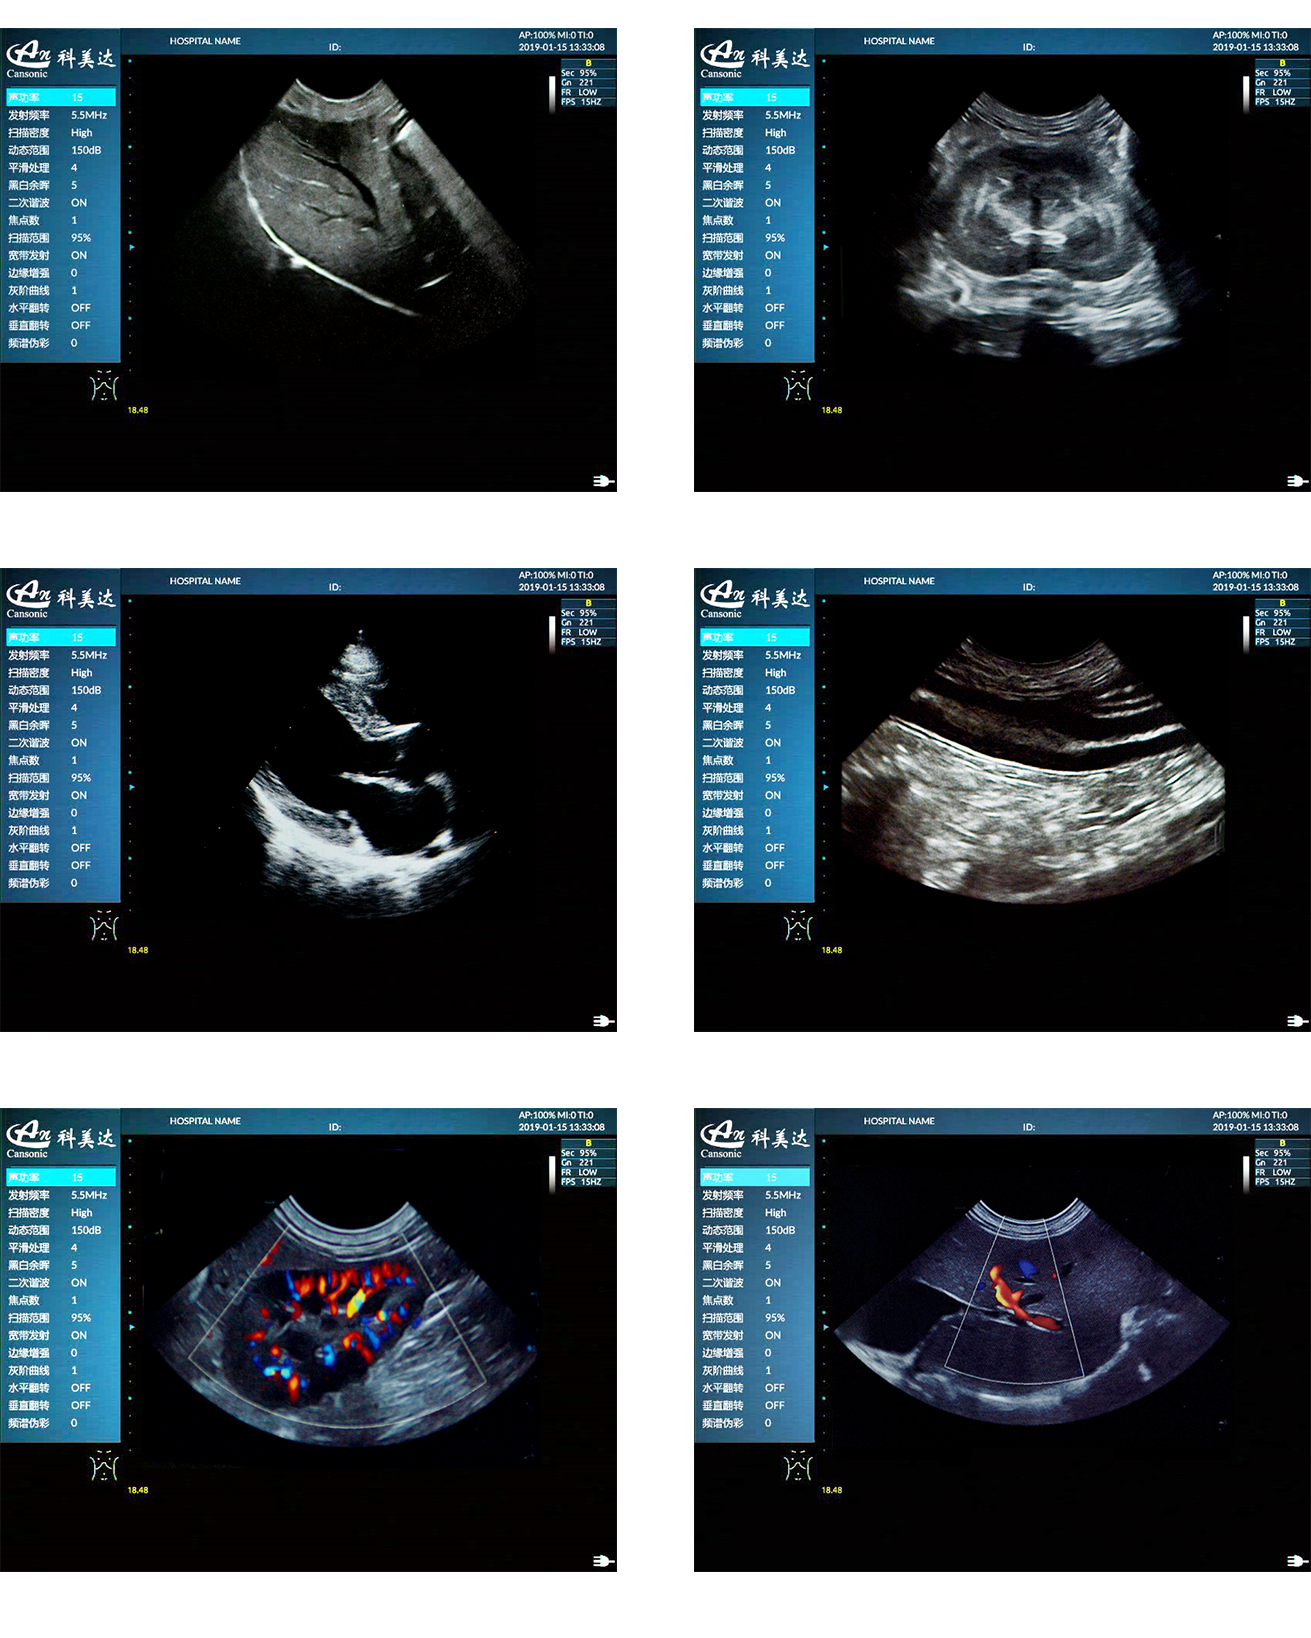

臨床圖示

2、適用于狗、貓、馬、牛、羊等多種動物的腹部、生殖、血管小器官,肌骨等檢查模式

5、能量多普勒POWER成像模式、彩色多普勒Color成像模式等模式適用于應用掃查